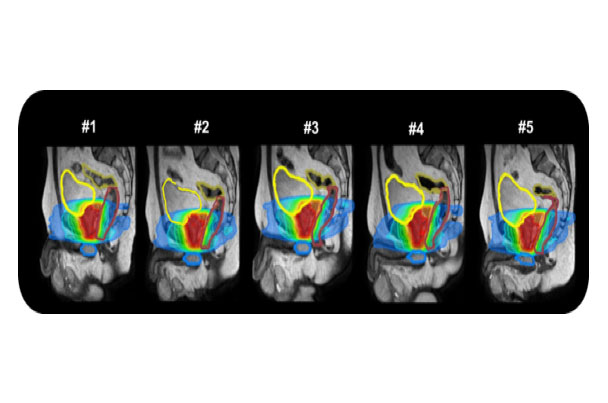

随着生活水平的提高,前列腺癌大发病逐渐上升,剂量学研究和初步的临床实践已经显示调强是当今放疗前列腺癌的最好照射技术,有广泛的应用前景,磁共振引导技术可以更好的对前列腺组织进行分辨,可以进行功能保留行治疗及肿瘤消融治疗,同时磁共振功能成像技术也为治疗疗效提供生物学依据。

磁共振实时成像可动态监测由于膀胱充盈不同或肠道蠕动带来的靶区位置形状改变,并进行自适应计划调整,更好的提高靶区剂量覆盖。